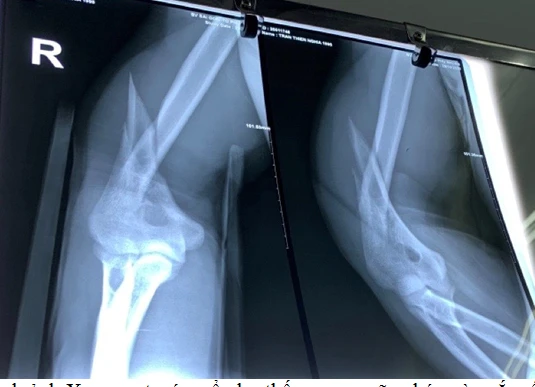

Hình chụp X-quang trước mổ cho thấy xương gãy chéo và xoắn phức tạp. Ảnh: BVCC

BS Khánh còn cho biết do cơ chế vật tay nên khi gãy xương cánh tay đa phần đường gãy chéo dài và xoắn phức tạp nên nguy cơ tổn thương thần kinh quay rất cao. Anh N. may mắn không rơi vào trường hợp nói trên.